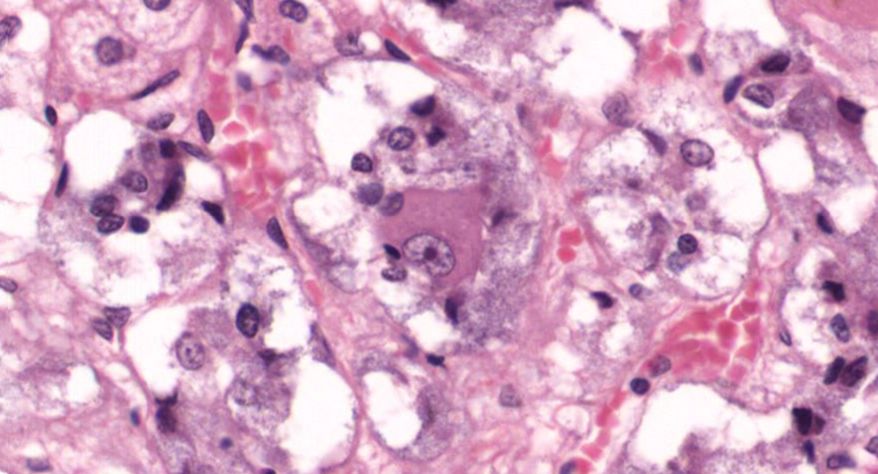

糖尿病肾病:1.大部分肾小球系膜区大量基质增多,较多形成结节状扩大,少数细胞靠结节边缘排列, 形成典型的K-W结节。部分节段有系膜细胞轻度增生, 基膜增厚。2.少数小球伴有球囊壁纤维化。 少部分肾小球硬化(玻璃样小体)。3.肾小管较多灶性萎缩,部分肾小管扩张,管腔内有蛋白管型。4.间质广泛纤维化,伴大量炎症细胞浸润(淋巴细胞、浆细胞)。许多肾小球入球细动脉壁增厚玻变, 间质肌性小动脉内膜增厚纤维化。

1.全景图

2.肾小球多个W-K结节形成

3.肾小球硬化

4.肾小管扩张

5.入球微动脉管壁增厚